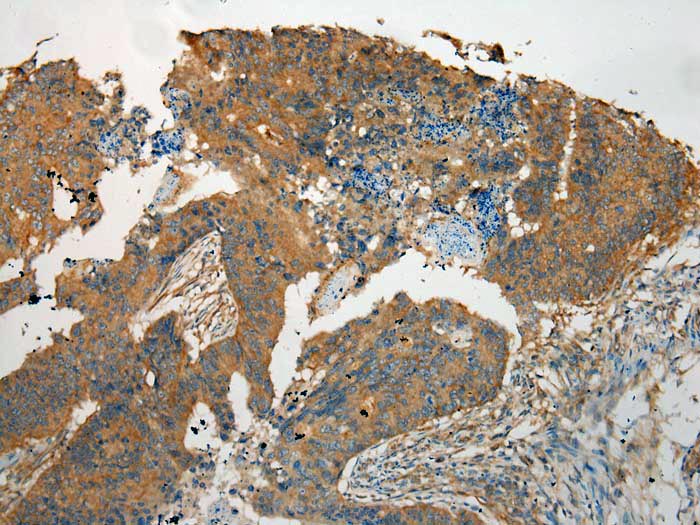

Immunohistochemical analysis of paraffin-embedded Human Colorectal cancer tissue using #40160 at dilution 1/100.

Immunohistochemical analysis of paraffin-embedded Human Tonsil cancer tissue using #40160 at dilution 1/100.